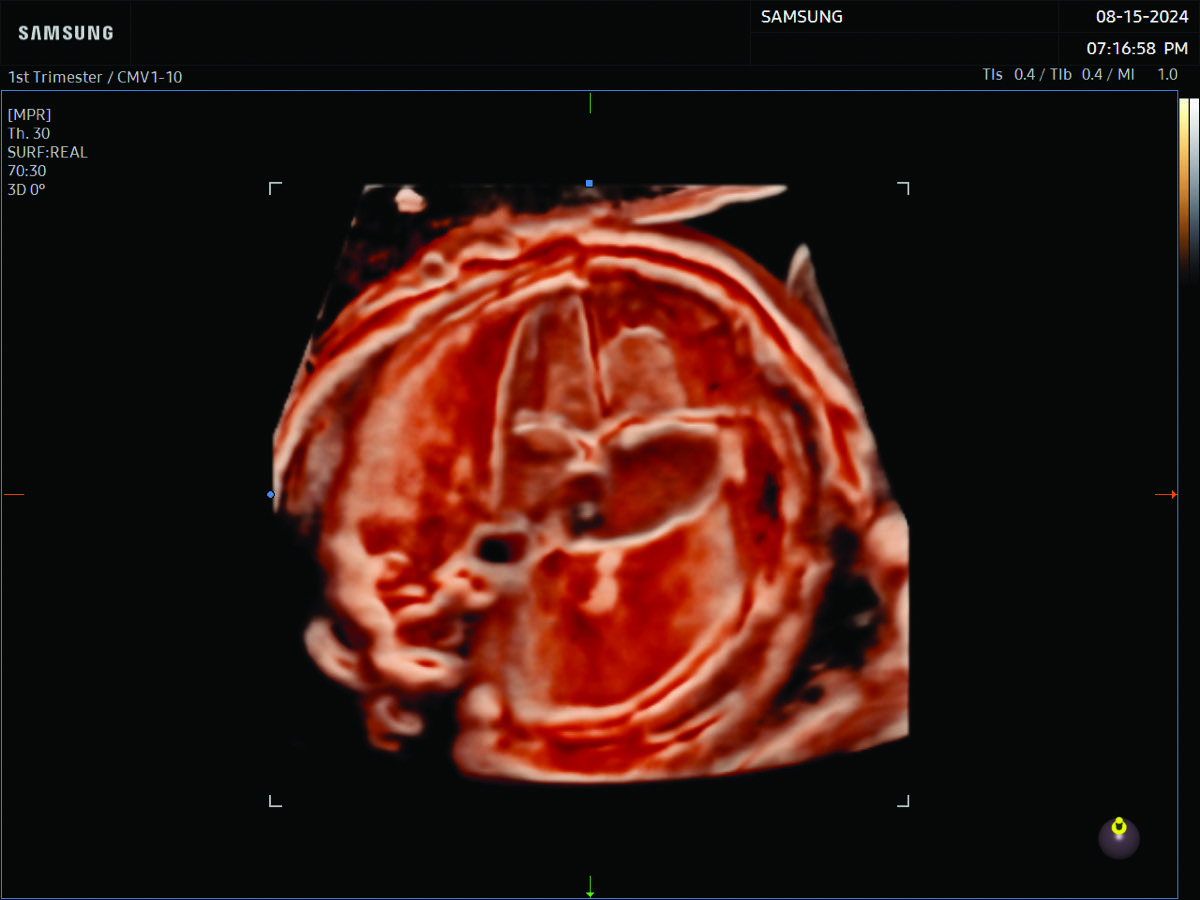

Comprehensive, advanced and expert MFM care for high-risk pregnancies

- Fetal anomalies